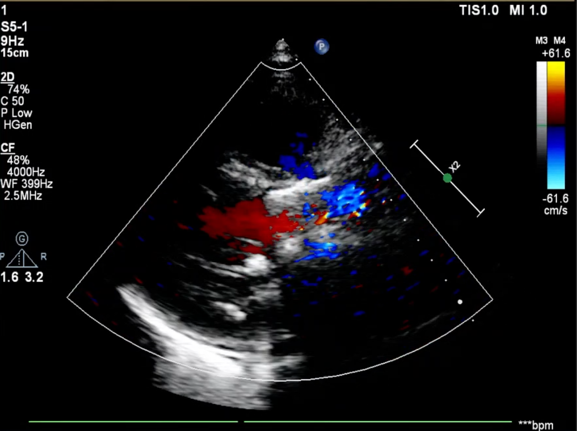

患者为76岁女性,术前超声心动图提示主动脉瓣重度狭窄并轻度关闭不全、峰值流速 5.1m/s、平均跨瓣压差 71mmHg、有效瓣口面积 0.32cm²;双房增大,升主动脉瘤样扩张,左室后壁增厚;二尖瓣轻度反流、三尖瓣中度反流;LVEDd:49mm,LVEF:29%,左心功能减退。

手术采用22 mm TaurusAtlas球囊进行预扩,植入AV23TaurusNXT主动脉瓣。第一次释放后位置偏高,瓣膜完全回收。第二次释放到工作位,检测左右冠血流灌注情况,考虑左瓣叶的瓣尖钙化影响左冠脉血流,使用第二次回收后,预置LCA保护。之后再次释放瓣膜至工作位,在GuidezillaII支撑保护下送 4.0×18mm 支架至 LAD 近段,之后瓣膜精准释放,后用22mm TaurusAtlas球囊后扩。术后即刻经胸超声心动图评估显示少量瓣周漏,平均跨瓣压差为10mmHg,主动脉瓣口峰值流速为2.3m/s,有效瓣口面积为1.80cm²,血流动力学指标理想。

超声影像

血流动力学改善,瓣膜形态良好,少量瓣周漏